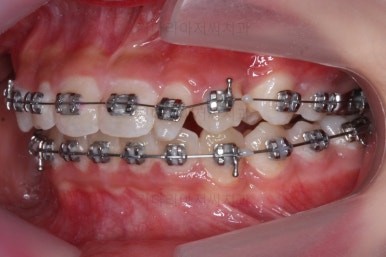

왜소치 좌우로 틈을 일부러 만든 상태입니다.

그 후에 임시 개념으로 사이즈를 크게 만들어 줬어요.

사이즈를 크게 한 뒤에도 약간의 틈이 남아서 다시 틈을 줄여주는 과정을 진행했어요.

아무래도 치아 크기의 문제가 있다보니 완벽한 교합을 맞추기는 힘들었짐나 가능한 마무리를 더 해보기로 했어요.